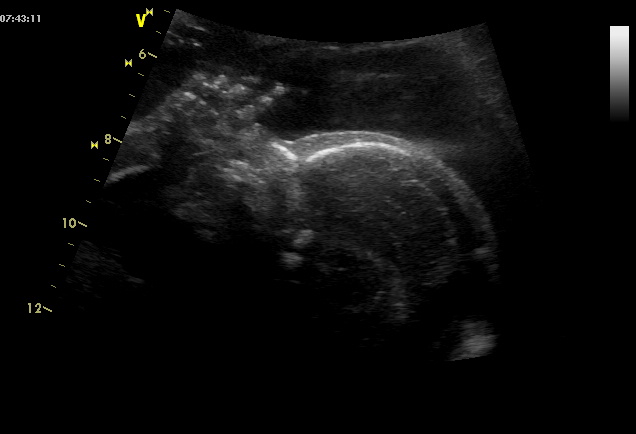

Dnes 2. screening a čekáme chlapečka, rozhodli jsme se pro Adámka.